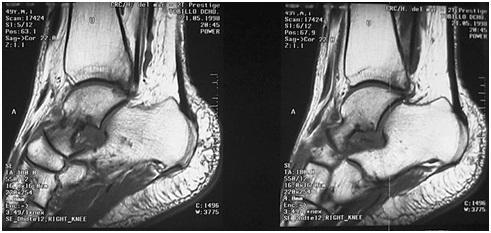

Quisiera mandarles uns rsdiografia de una reciente operacion